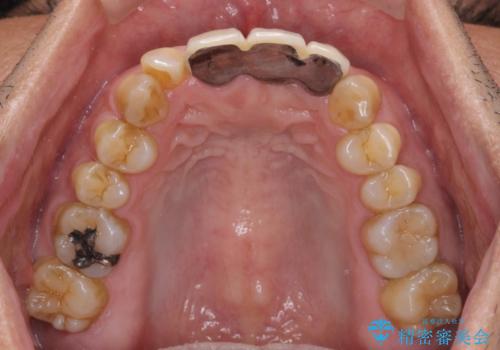

- 保険診療の前歯のブリッジが、形態も色も不自然で気になるとのことで来院された患者様です。

神経の抜かれている土台の歯は根管治療を行った上で、オールセラミックブリッジにより補綴することとしました。